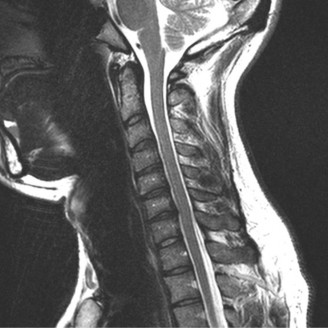

When surgical intervention becomes unavoidable, meticulous pre-operative planning is the cornerstone of a successful outcome. Advanced imaging is non-negotiable. An MRI with and without gadolinium contrast is the gold standard for defining the extent of the epidural abscess, the degree of neural compression, and the involvement of adjacent paraspinal musculature (e.g., psoas abscess). T1-weighted images typically show hypointense signals in the infected marrow, while T2-weighted and STIR sequences reveal hyperintense fluid and edema in the disc space and vertebral bodies. Gadolinium enhancement highlights the vascularized inflammatory phlegmon and the capsule of any abscesses.

In addition to MRI, a fine-cut computed tomography (CT) scan is essential for evaluating bony destruction. CT allows the surgeon to assess bone stock for pedicle screw purchase and to template the size of the interbody cages required for anterior column reconstruction. Upright standing radiographs (if the patient can tolerate them) or full-length supine films are necessary to evaluate global spinal alignment and regional kyphosis.